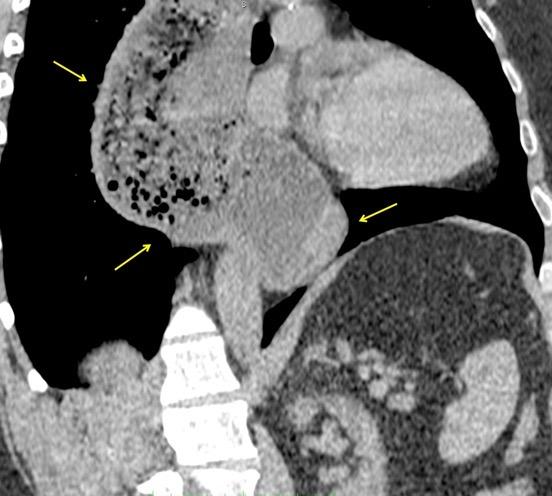

Rotura aneurisma de Aorta descendente.

Dolor. (10 días antes: "Rotura inminente”)